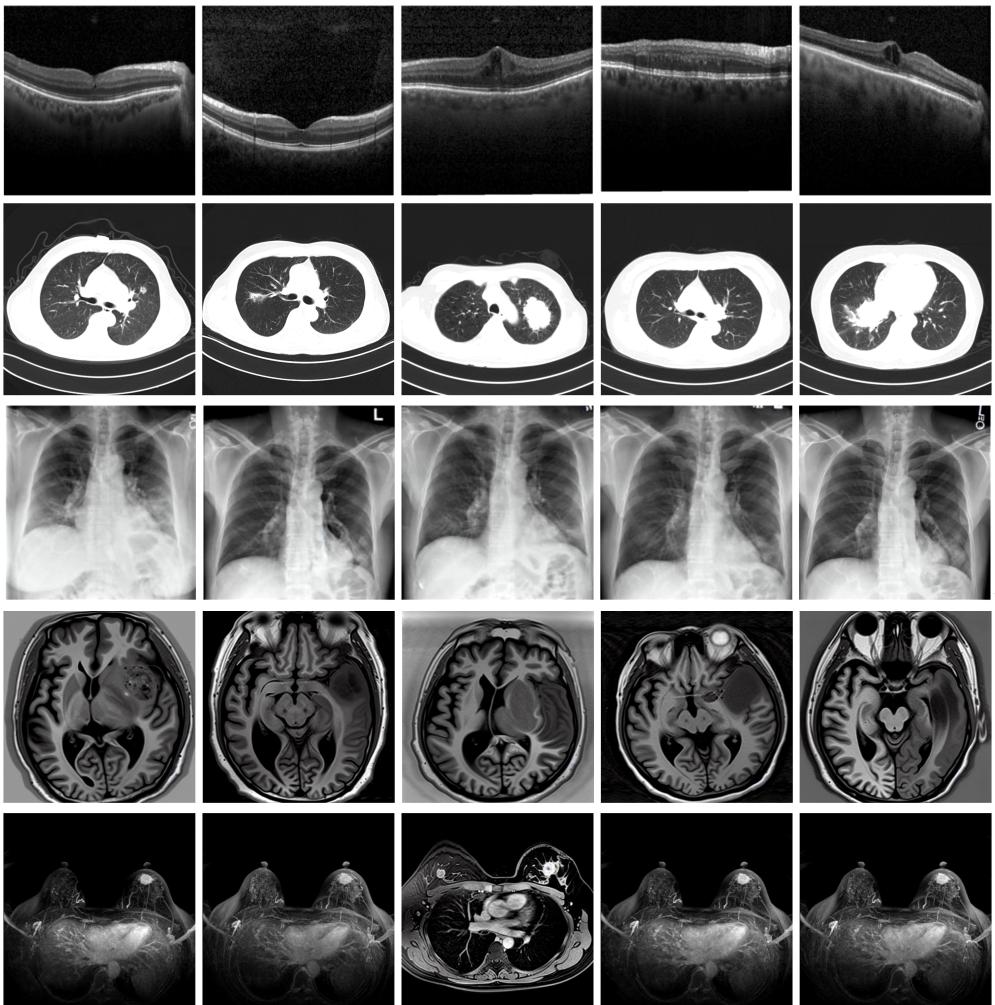

圖為由MINIM生成的高質(zhì)量醫(yī)學(xué)合成圖像(受訪者供圖)

“目前公開的醫(yī)學(xué)影像數(shù)據(jù)非常有限,我們建立的生成式模型有望解決訓(xùn)練數(shù)據(jù)不夠的問題?!北本┐髮W(xué)未來技術(shù)學(xué)院助理研究員王勁卓說,研究團隊利用多種器官在CT、X光、磁共振等不同成像方式下的高質(zhì)量影像文本配對數(shù)據(jù)進行訓(xùn)練,最終生成海量的醫(yī)學(xué)合成影像,其在圖像特征、細(xì)節(jié)呈現(xiàn)等多方面都與真實醫(yī)學(xué)圖像高度一致。

實驗結(jié)果顯示,MINIM生成的合成數(shù)據(jù)在醫(yī)生主觀評測指標(biāo)和多項客觀檢驗標(biāo)準(zhǔn)方面達國際領(lǐng)先水平,在臨床應(yīng)用中具有重要參考價值。在真實數(shù)據(jù)基礎(chǔ)上,使用20倍合成數(shù)據(jù)在眼科、胸科、腦科和乳腺科的多個醫(yī)學(xué)任務(wù)準(zhǔn)確率平均可提升12%至17%。